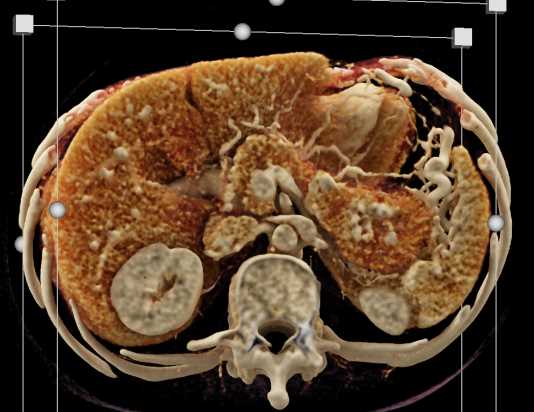

Neuroendocrine Tumor Pancreas